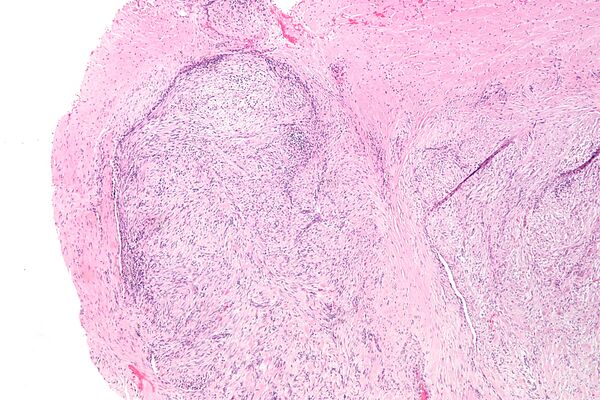

Микроскопическая гистопатология опухолей узелкового фасциита, окрашенных гематоксилином и эозином, состоит из веретенообразных миофибробластических клеток[8]. Эти клетки находятся в миксоидной или коллагеновой (с высоким содержанием коллагеновых волокон) ткани. Неопластические миофибробласты расположены в виде завитков и/или коротких пучков. Эти клетки могут демонстрировать высокую скорость репликации, если судить по их митотическому индексу, но эти митозы выглядят нормально. Опухолевые ткани часто содержат эритроциты, лимфоциты и гигантские остеокластоподобные клетки, а также могут содержать участки костеподобной ткани[11].

Иммуногистохимические анализы показывают, что клетки при узелковом фасциите обычно экспрессируют гладкомышечный актин, мышечно-специфический актин и белки виментина, но, как правило, не экспрессируют белки CD34, S-100, десмин, трипсин, фактор VIII, F4/80или HLA-DR1[11]. Необычно то, что клетки в опухолях узелкового фасциита экспрессируют белок CD68 (гистиоцит-специфический маркер)[7]